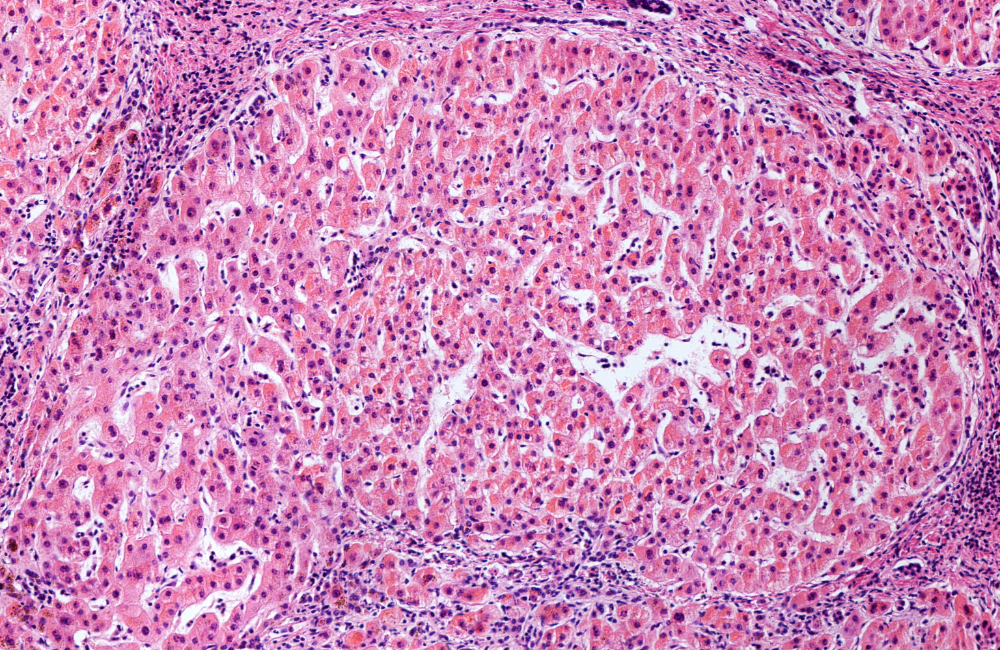

Cirrhosis is a late stage of scarring (fibrosis) of the liver caused by many forms of liver diseases and conditions, such as hepatitis and chronic alcoholism. Each time your liver is injured—whether by disease, excessive alcohol consumption, or another cause—it tries to repair itself. In the process, scar tissue forms. As the cirrhosis progresses, more and more scar tissue forms, making it difficult for the liver to function.